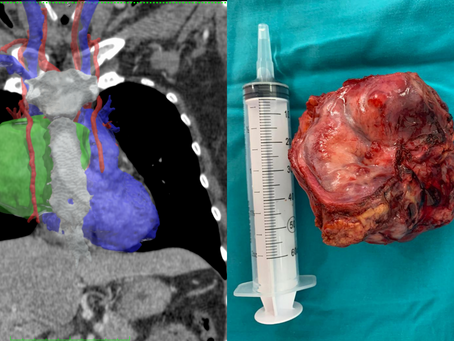

Planificación avanzada para resección de tumor mediastinal

23 jul 2021